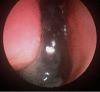

A woman in her late 70s with chronic bilateral epiphora under ophthalmology review was referred to our department for dacryocystorhinostomy after punctoplasty and detection of nasolacrimal duct obstruction. A CT scan of the paranasal sinuses for preoperative planning revealed complete opacification of the right maxillary, anterior ethmoid, frontal and sphenoid sinuses, left septal deviation and an incidental finding of foreign bodies in the right anterior nasal airspace. She proceeded with functional endoscopic sinus surgery (FESS) and removal of foreign bodies. To our surprise, a partially eroded 20 pence and 1 penny coin were found and removed from her right nasal airway. There was no history given about foreign bodies in her nose. Her symptoms improved postoperatively.